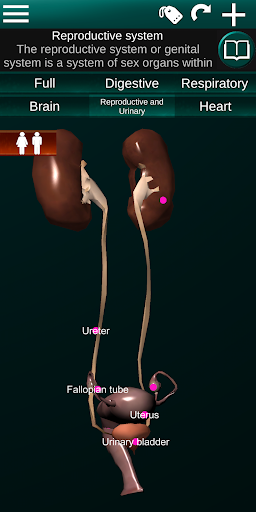

* Sistem reproduksi, yang meliputi organ reproduksi pria dan wanita.

* Bandingkan organ pria dan wanita.